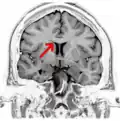

-

Coronal T2 (grey scale inverted) MRI of the brain at the level of the caudate nuclei emphasizing corpus callosum -